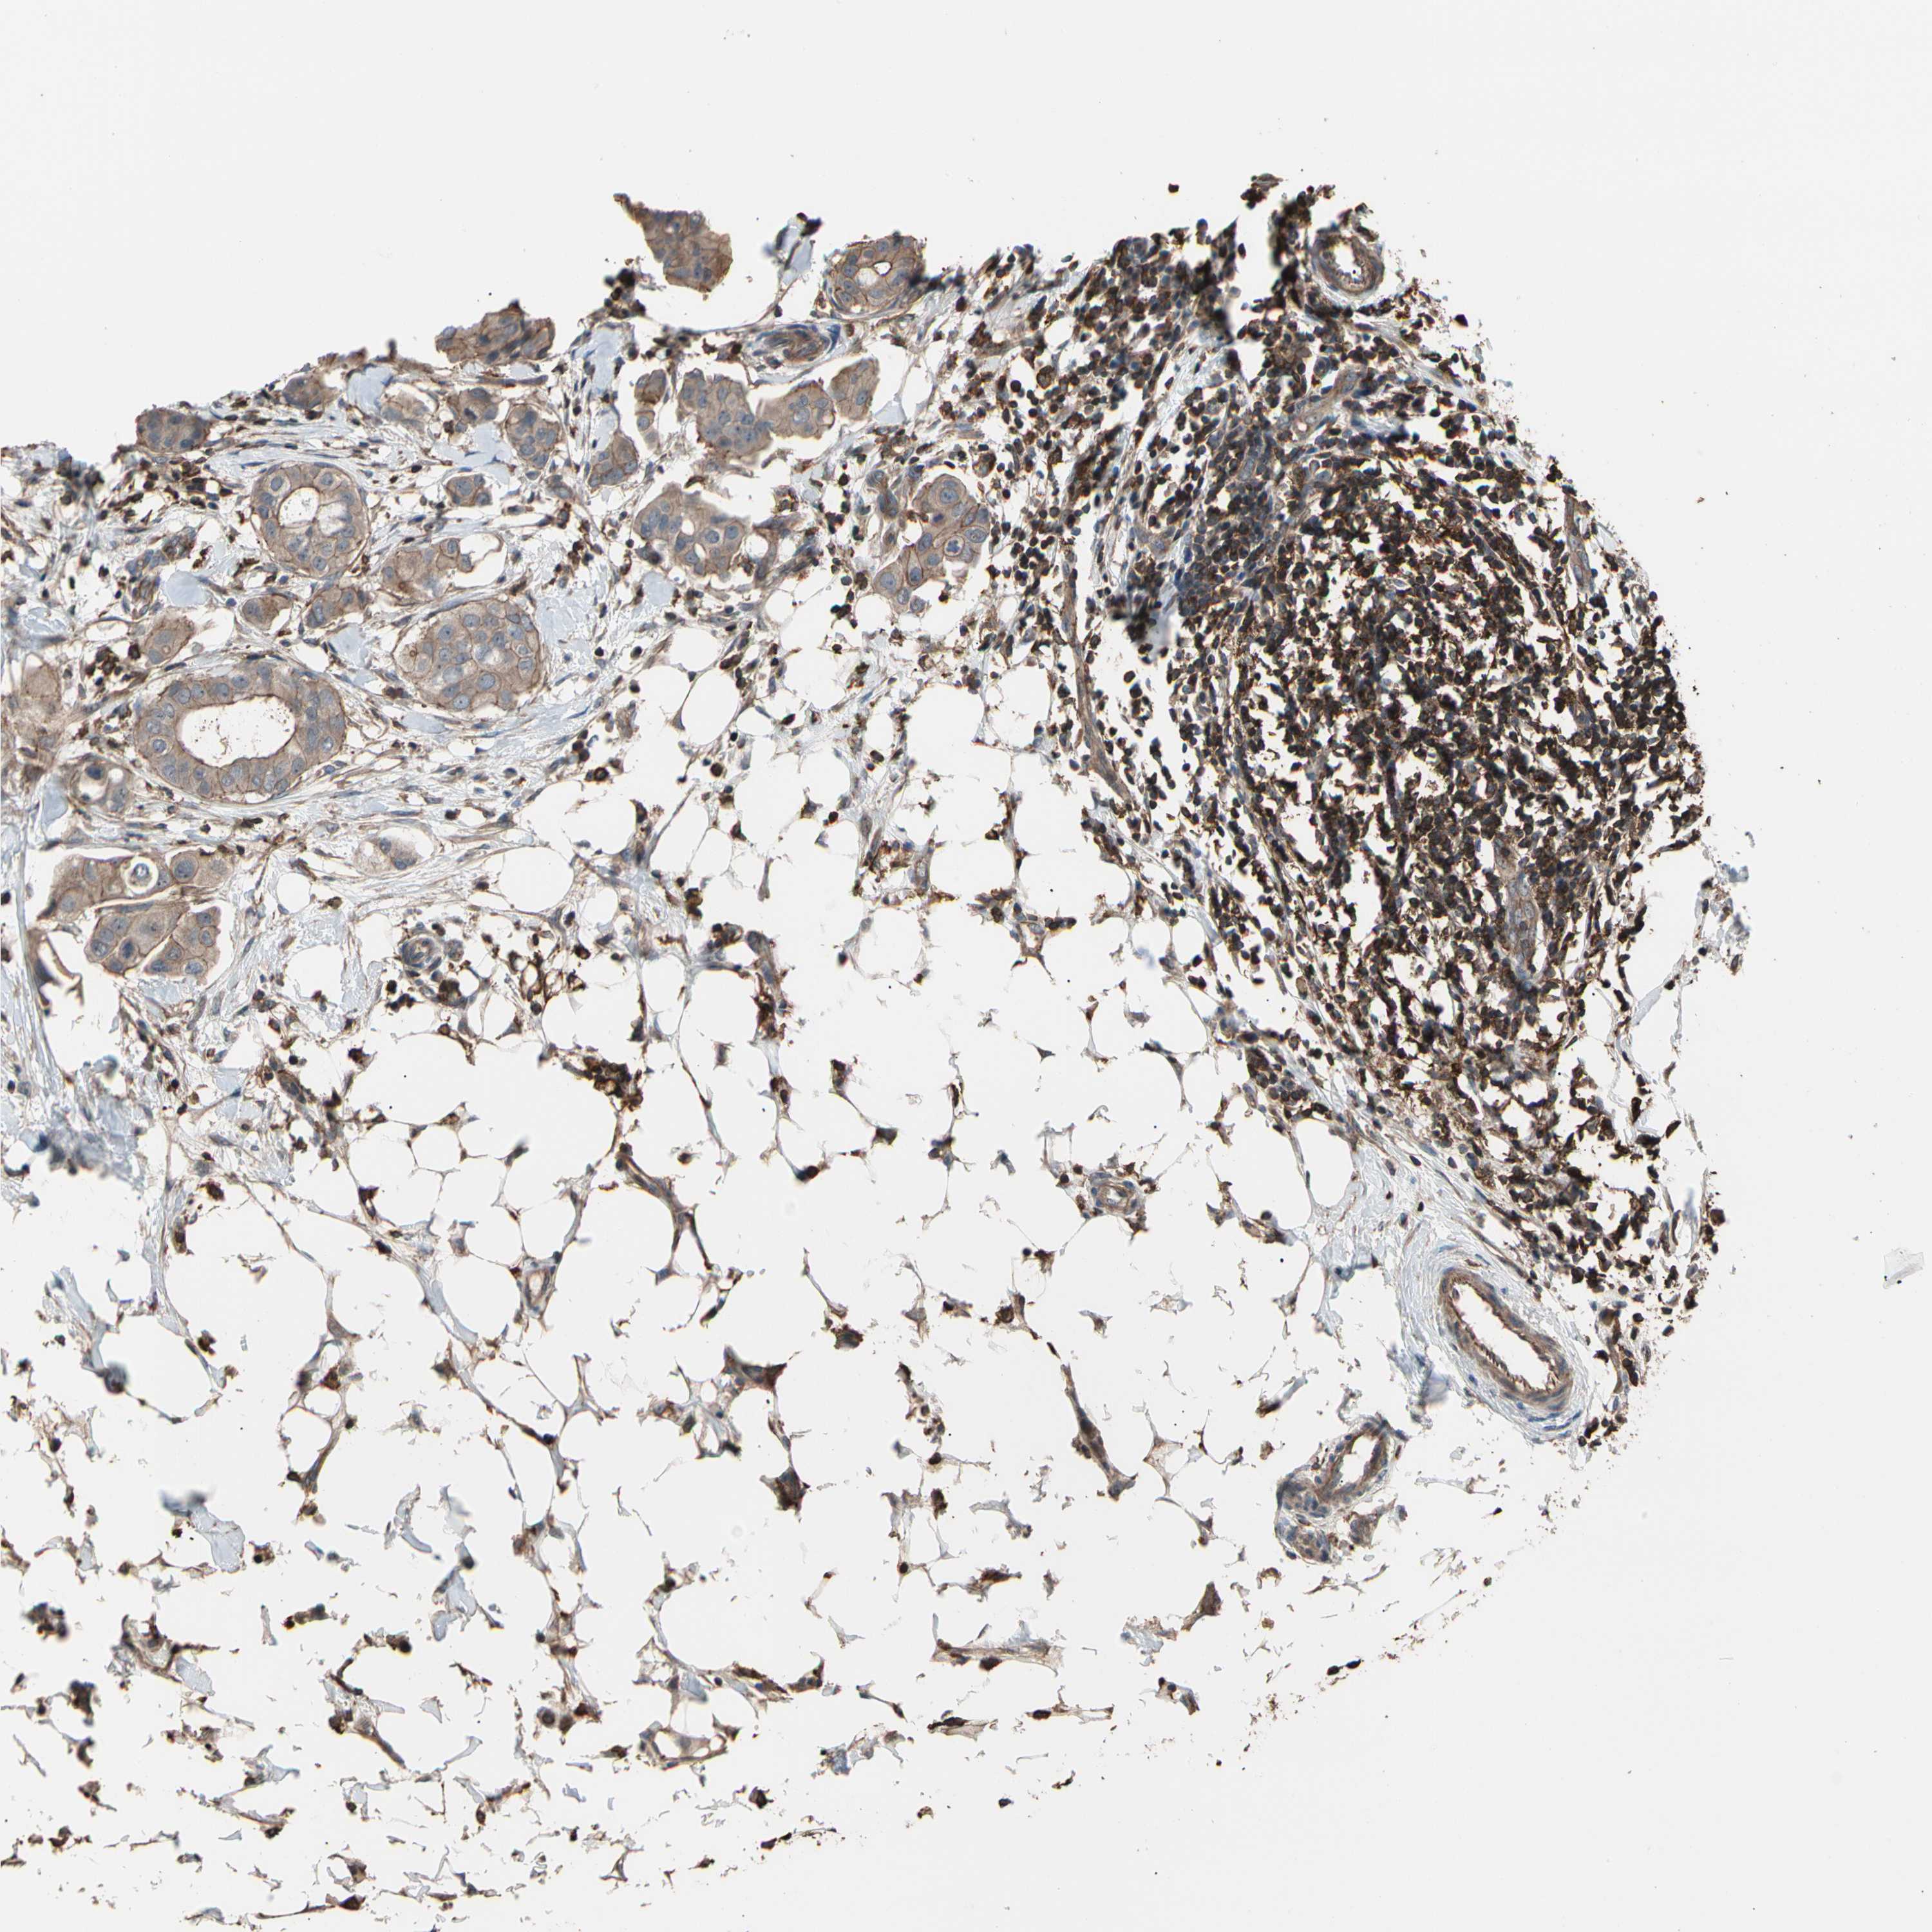

BRCA TCGA BRCA VALIDATION PROTEIN EXPRESSION